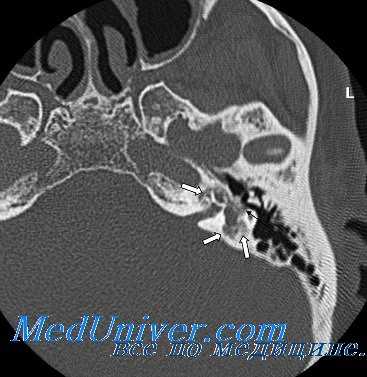

КТ височных костей. С обеих сторон диффузное снижение пневматизации ячеек сосцевидного отростка и пирамиды височной кости за счет отосклероза